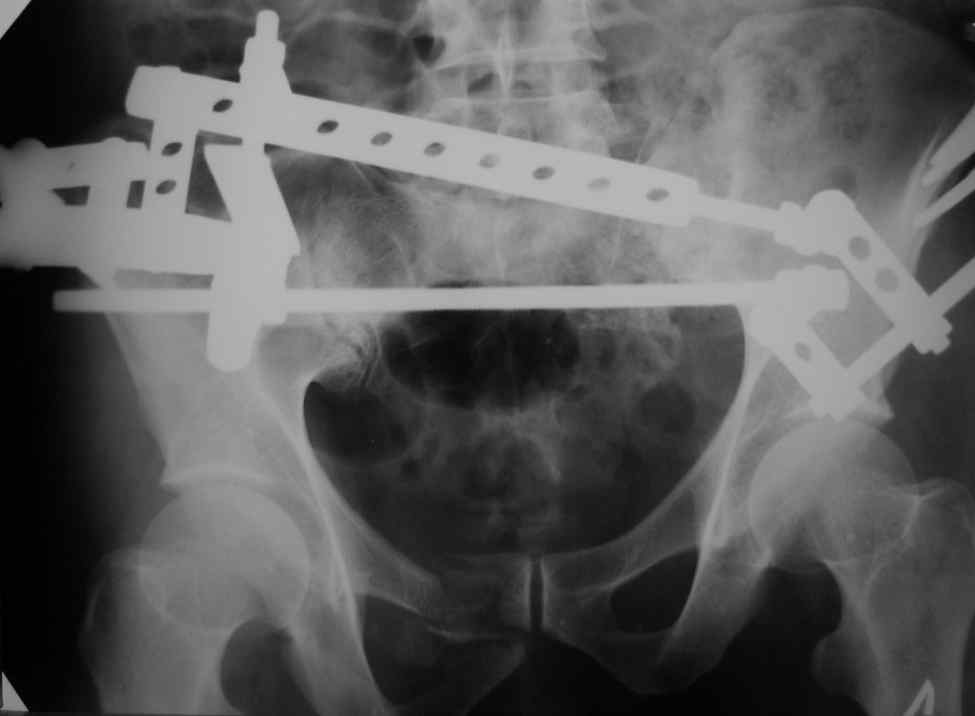

Re: Введение илиосакральных винтов

Александр Николаевич! Походу самим не справиться (может к себе возмете, а?) Мы бы съездили к вам посмотрели как это делается!

Снимки вот